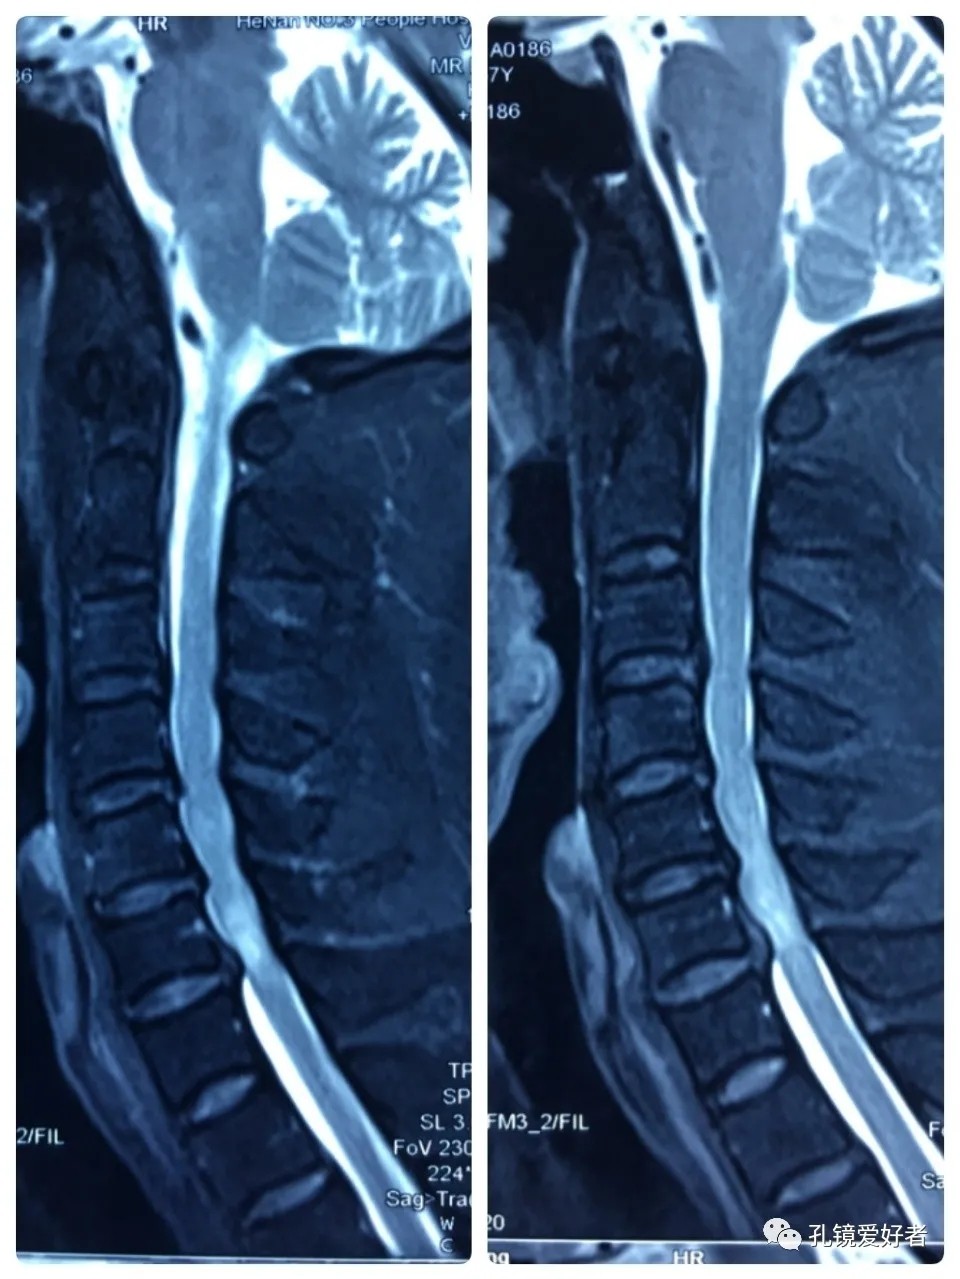

MRI - Sagittal Position

Plain MRI Scan

The patient's preoperative imaging data

Then let's look at MRI.

The MRI shows that the cervical stenosis is on C3-4, C5-6 and C6-7. Considering the patient's clinical symptoms, C5-6 and C6-7 are the main affected segments. So it’s advised that the patient undergo posterior cervical open-door laminoplasty. According to the patient, he had visited many hospitals before and received similar proposals of diagnosis and treatment- posterior cervical open-door laminoplasty. The reason he came to our hospital was that he wanted his surgery could be performed in a minimally invasive way. After considerable preoperative discussion with my colleagues and the patient, we decided to perform the minimally invasive endoscopic decompression for C5-6 and C6-7 double-segment stenosis through posterior approach (with the Delta system).